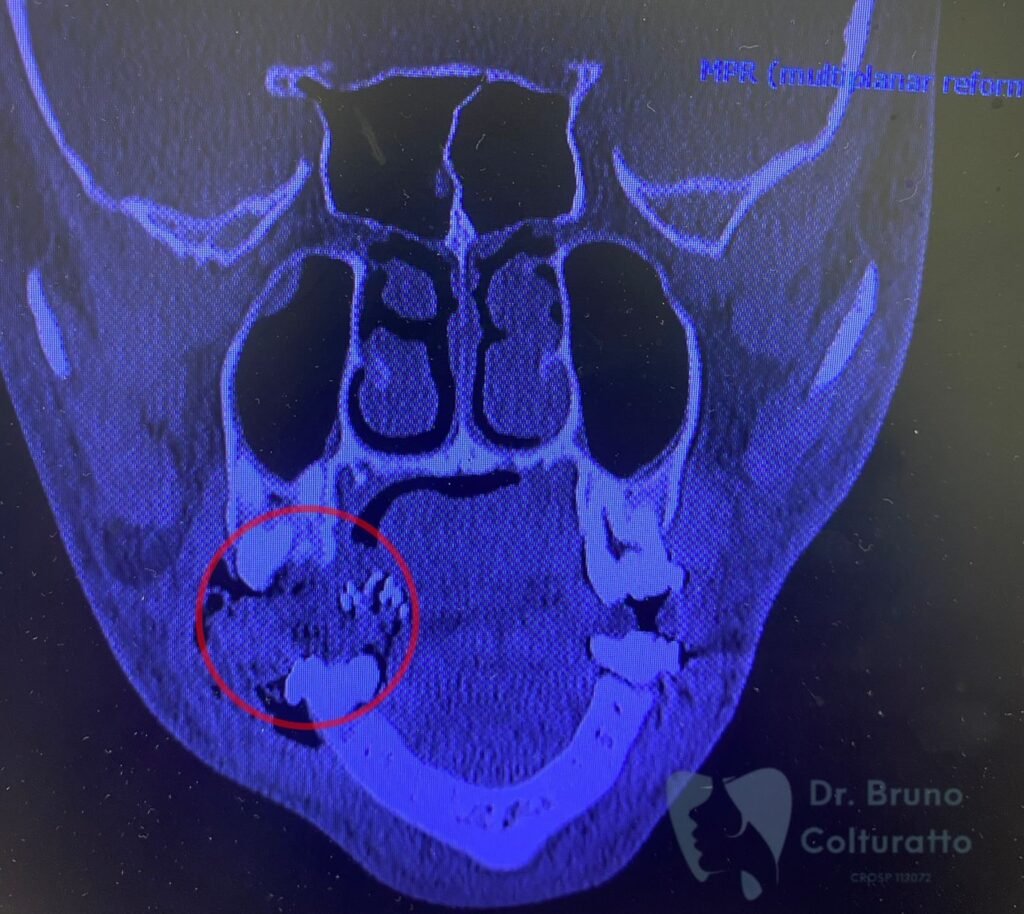

A Patologia Oral e Maxilofacial é a especialidade responsável pelo diagnóstico e tratamento de doenças que afetam a boca, mandíbula e estruturas faciais. Atua na identificação de lesões, cistos e tumores, garantindo diagnóstico preciso e tratamento adequado para preservar a saúde bucal e geral do paciente.